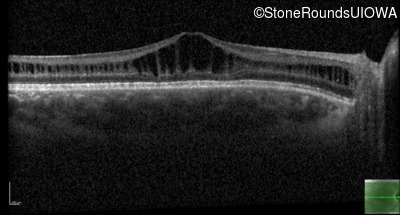

Age at visit: 11 years

OD OS

This 11 year old male was never correctable to 20/20. He received glasses at age 1 for esotropia. His refraction is +4.25 +2.00 x 105 OD and +2.00 +2.00 x 80 OS.